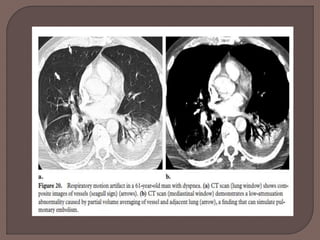

 Respiratory motion artifacts are the most

common cause of indeterminate CT

pulmonary angiography and can cause

misdiagnosis of pulmonary embolism. These

artifacts are best seen with lung window

settings and can create the “seagull” sign

Image inferior to superior